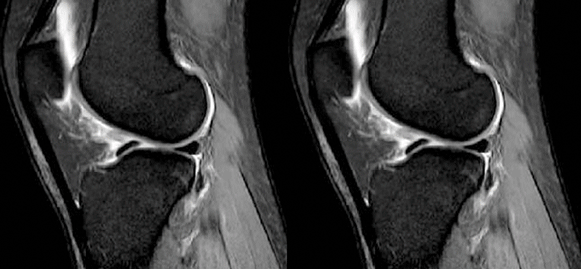

4)消失:

-

髁间窝空虚,无韧带信号。

见于较久的损伤,损伤的ACL撕裂较重呈马尾状,无滑膜包裹,逐渐被关节内的酶腐蚀而消失。